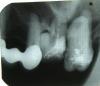

Lyu9mila Опубликовано 7 ноября, 2009 Автор Поделиться Опубликовано 7 ноября, 2009 Пока только этот Ссылка на комментарий

Bier Опубликовано 7 ноября, 2009 Поделиться Опубликовано 7 ноября, 2009 так там то ли забытый корень от 17го то ли оголенный корень от 16, вот и не заживает ничего. Сделайте еще прицельный снимок зоны 17,16. Ссылка на комментарий

доминика Опубликовано 7 ноября, 2009 Поделиться Опубликовано 7 ноября, 2009 (изменено) Пока только этоту вас большая киста на 16,переодически обострясь ,открывается свищ-дырка ,можно попробовать перелечить каналы в нем ,сделайте прицельный снимок 16 так там то ли забытый корень от 17го то ли оголенный корень от 16, вот и не заживает ничего. Сделайте еще прицельный снимок зоны 17,16.угу или забыли корень с кистой....а в 25 стоит похоже скрепка ух ты... Изменено 7 ноября, 2009 пользователем доминика Ссылка на комментарий

Ion Опубликовано 7 ноября, 2009 Поделиться Опубликовано 7 ноября, 2009 В принципе, можно и перелечить шестёрку. Но на удалёном зубе видно, похоже на кисту, а также наверно прйдётся лечить и тот зуб, где является киста,т.е.на н/ч справо. Ссылка на комментарий

Lyu9mila Опубликовано 7 ноября, 2009 Автор Поделиться Опубликовано 7 ноября, 2009 Спасибо за активность. На №16 - "карман" - так сказал доктор. И рано или поздно его нужно удалить. "Карман" - это киста? Ссылка на комментарий

доминика Опубликовано 7 ноября, 2009 Поделиться Опубликовано 7 ноября, 2009 Спасибо за активность. На №16 - "карман" - так сказал доктор. И рано или поздно его нужно удалить. "Карман" - это киста?больше на кисту похоже ,может сочетанно,прицельный сделайте ,а вообще займитесь ртом, проблем целая куча и протезироваться вам надо Ссылка на комментарий

x3m Опубликовано 7 ноября, 2009 Поделиться Опубликовано 7 ноября, 2009 (изменено) ...а в 25 стоит похоже скрепка ух ты... это армирование такое. скрепочный штиВт.Извиняюсь, т.е.слевой стороны на н/ч. ! По ошибке, торопясь так вышло... да где ж на н/ч киста-то? может, второпях с в/ч попутали? ...а ороантрального соустья не могЁт там быть?или таки резидуальная киста 17?ЗЫ. имхо, 16 уходит. лечить там нечего. Дистальный корень висит в пустоте.ув. Lyu9mila, повесьте прицельный снимок. без него - ну никак. всё предположения только Изменено 7 ноября, 2009 пользователем x3m Ссылка на комментарий

Lyu9mila Опубликовано 7 ноября, 2009 Автор Поделиться Опубликовано 7 ноября, 2009 (изменено) Новые снимки. Прицельный: №16, №17- до удаления 17. И гайморовы пазухи на сегодняшний день. К стоматологу хожу 2 раза в год, а картина получается такая, что словно я с луны свалилась или из пещеры вылезла. Может возраст? С весны, когда "полетел" мост, проблемы с ртом повисли на мне тяжким бременем. И всё сложно. и трудно решимо, и одномоментно ( терапия, хирургия, протезирование). И самое тяжкое - принятие решение за мной!!! А что я могу? С нумерацией зубов разбиралась неделю... Грустно. Всем спасибо. Изменено 7 ноября, 2009 пользователем Lyu9mila Ссылка на комментарий

доминика Опубликовано 7 ноября, 2009 Поделиться Опубликовано 7 ноября, 2009 Если в 16 еще и карман, он увы подлежит удалению ,начните заниматься ртом и в первую очередь найдите хорошего ортопеда ,вашу ситуацию в отделе протезирования повесьте, вам расскажут какие возможны варианты, с чего начать Не расстраивайтесь ,все будет хорошо Ссылка на комментарий